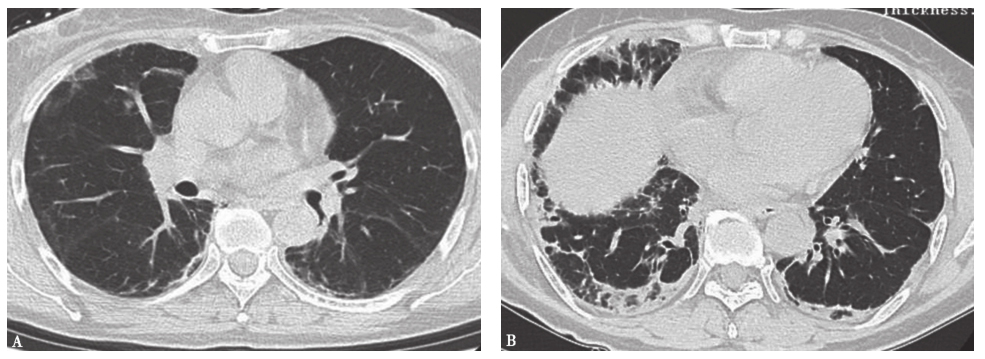

(4)结缔组织疾病相关间质性肺疾病:结缔组织疾病(CTD)是一组异质性、免疫介导、可累及多个器官的炎症性病变,主要包括类风湿关节炎(rheumatoid arthritis,RA)、系统性红斑狼疮(systemic lupus erythematosus,SLE)、 多发性肌炎(polymyositis,PM)/皮肌炎(dermatomyositis,DM)、系统性硬化症(systemic sclerosis,SSc)、干燥综合征(Sjogren syndrome,SS)等。CTD的主要病理改变为疏松结缔组织发生黏液性水肿、类纤维蛋白变性、小血管坏死和组织损伤。肺支气管、肺血管及肺间质及胸膜含有丰富的结缔组织,因而成为重要的靶器官。CTD累及肺部的表现有间质性肺疾病、细支气管炎、肺血管病变及肺实质小结节等。病理类型可有普通型间质性肺炎、非特异性间质性肺炎、淋巴细胞间质性肺炎、机化性肺炎等。不同的病理类型有不同的HRCT表现(图4)。临床表现不仅有原发疾病表现也有肺部表现,诊断需要完善自身免疫相关疾病的诊断,必要时需要肺活检明确组织病理学类型,对于制订有效的治疗方案和判断患者预后至关重要。

图4皮肌炎合并机化性肺炎胸部CT表现

女性患者,46岁,活动后气喘1个月。胸部CT可见双肺磨玻璃高密度影伴实变病灶,沿支气管血管束走行分布。病理诊断为皮肌炎合并机化性肺炎